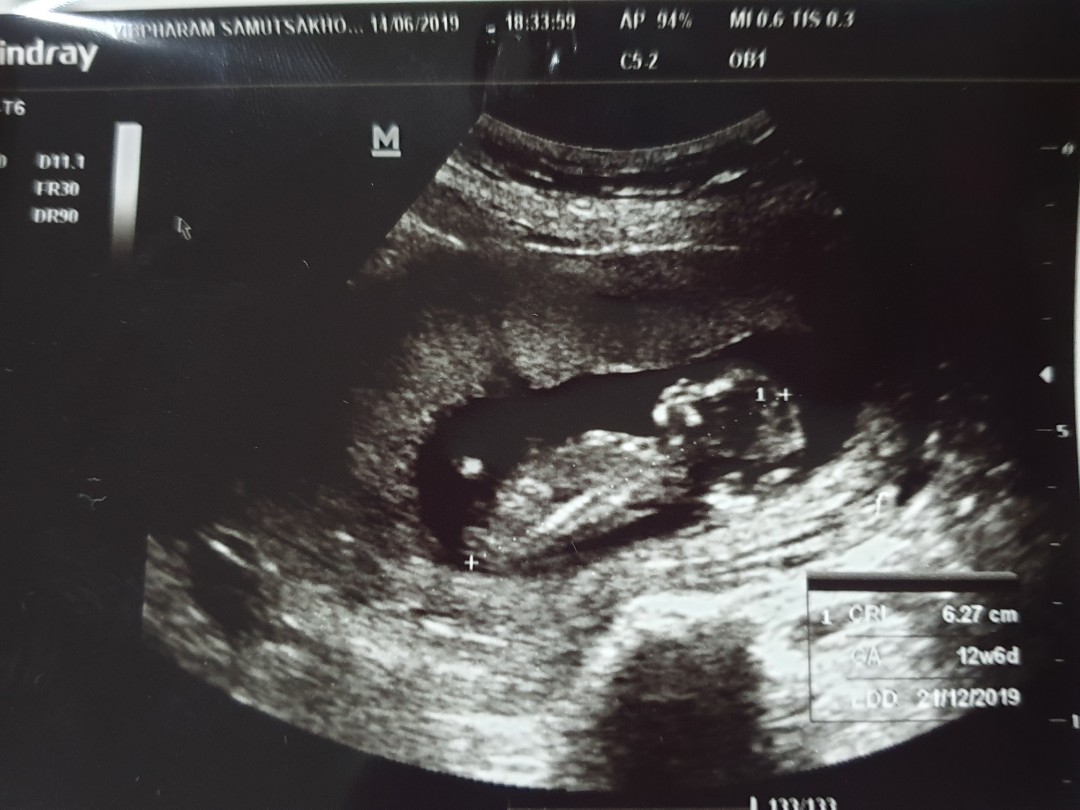

12 W 6D จร้า